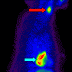

Anterior projection image of whole-body FDG-PET shows a large area of intense FDG uptake in the lower mediastinum (blue arrow). There is also a focus of intense activity in the left laryngeal region (red arrow). There is focal low-grade uptake at the right superior cardiac border, considered to represent physiologic uptake in the right atrium (green arrow). Physiologic uptake is noted in the ventricular myocardium (black arrow) and in the breasts (white arrows).

Lateral projection image of whole-body FDG-PET shows the focal increased FDG activity in the lower mediastinum (blue arrow) and in the neck (red arrow).